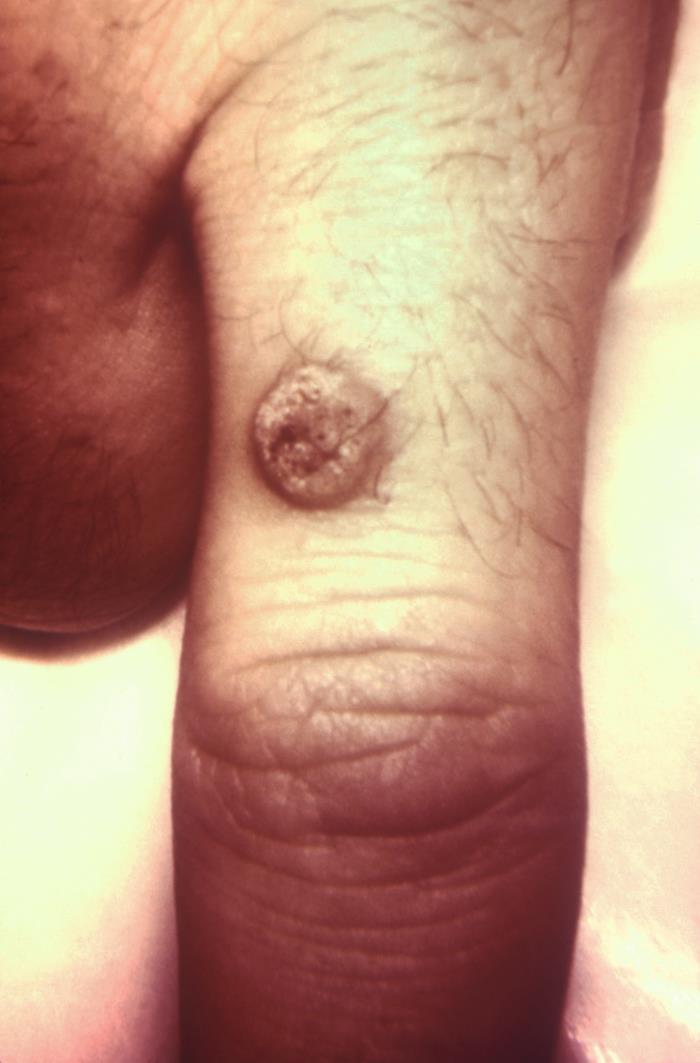

- Common warts (verruca vulgaris):

- The most common type of cutaneous wart.

- Most prevalent in young children.

- Usually on the hands.

- A typical lesion is a brown, exophytic, hyperkeratotic papule [Fig 1]

Common wart

Wart on finger, termed verruca vulgaris or the common wart.

Source CDC/R.S. Hibbets